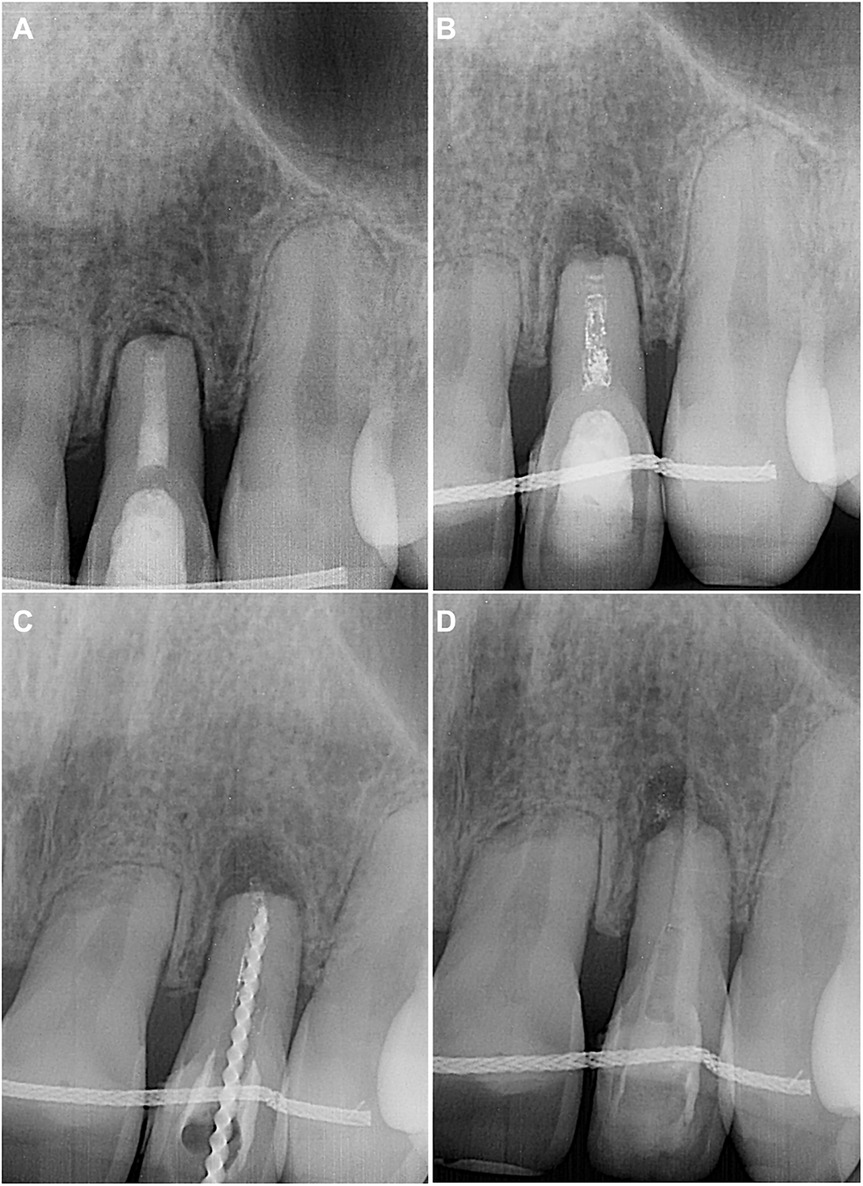

Although the second visit was scheduled after 2 weeks, the patient returned 4 weeks later due to his illness. The patient had no complaints, and no clinical signs were found for teeth 21–23 on examination. The periapical radiograph showed that the calcium hydroxide paste was washed out, and there was a periapical lesion on tooth 22 (Figure 2A). After the aforementioned anaesthesia protocol, isolation, and disinfection, the temporary filling was removed. The procedure was performed under a dental operating microscope, which confirmed the absence of visible cracks or fractures. The root canal was irrigated with 5 ml 3% NaOCl, 5 ml 17% EDTA, and 5 ml sterile physiological saline and then dried with sterile paper points. No additional shaping was performed at this stage, as the canal had already been enlarged during the initial instrumentation, and further preparation risked compromising the structurally weakened root. Due to the apical root resorption and the resulting direct communication with periapical tissues, the canal was filled with ProRoot MTA White (Dentsply Sirona Inc, Charlotte, NC). The material was mixed according to the manufacturer's instructions and condensed to a level 2 mm below the canal orifice. A moist sterile cotton pellet was placed, the access cavity was isolated with IRM, and the radiograph was taken to assess the quality of obturation (Figure 2B). After 48 h, the IRM and cotton pellet were removed, and fully set MTA was covered with a thin layer of glass ionomer cement Fuji IX (GC CORPORATION, Tokyo, Japan). The crown was restored with light-cured composite Charisma.

Figure 2. (A) Preoperative periapical radiograph demonstrating the empty root canal and periapical lesion of tooth 22. (B) Postoperative periapical radiograph after the root canal filling with ProRoot MTA White, followed by a wet cotton pellet and temporary restorative material IRM in the endodontic access cavity. (C) Six-month follow-up periapical radiograph showing a completely healed periapical lesion on tooth 22. (D) Eighteen-month follow-up periapical radiograph demonstrating no pathological changes in the tooth and periapical tissues.

The patient returned without complaints for scheduled follow-ups at 6 months (Figure 2C) and 18 months (Figure 2D). No clinical or radiological signs of endodontic pathology were found on examination. The periapical lesion of tooth 22 was completely healed. The next follow-up was scheduled after a year.